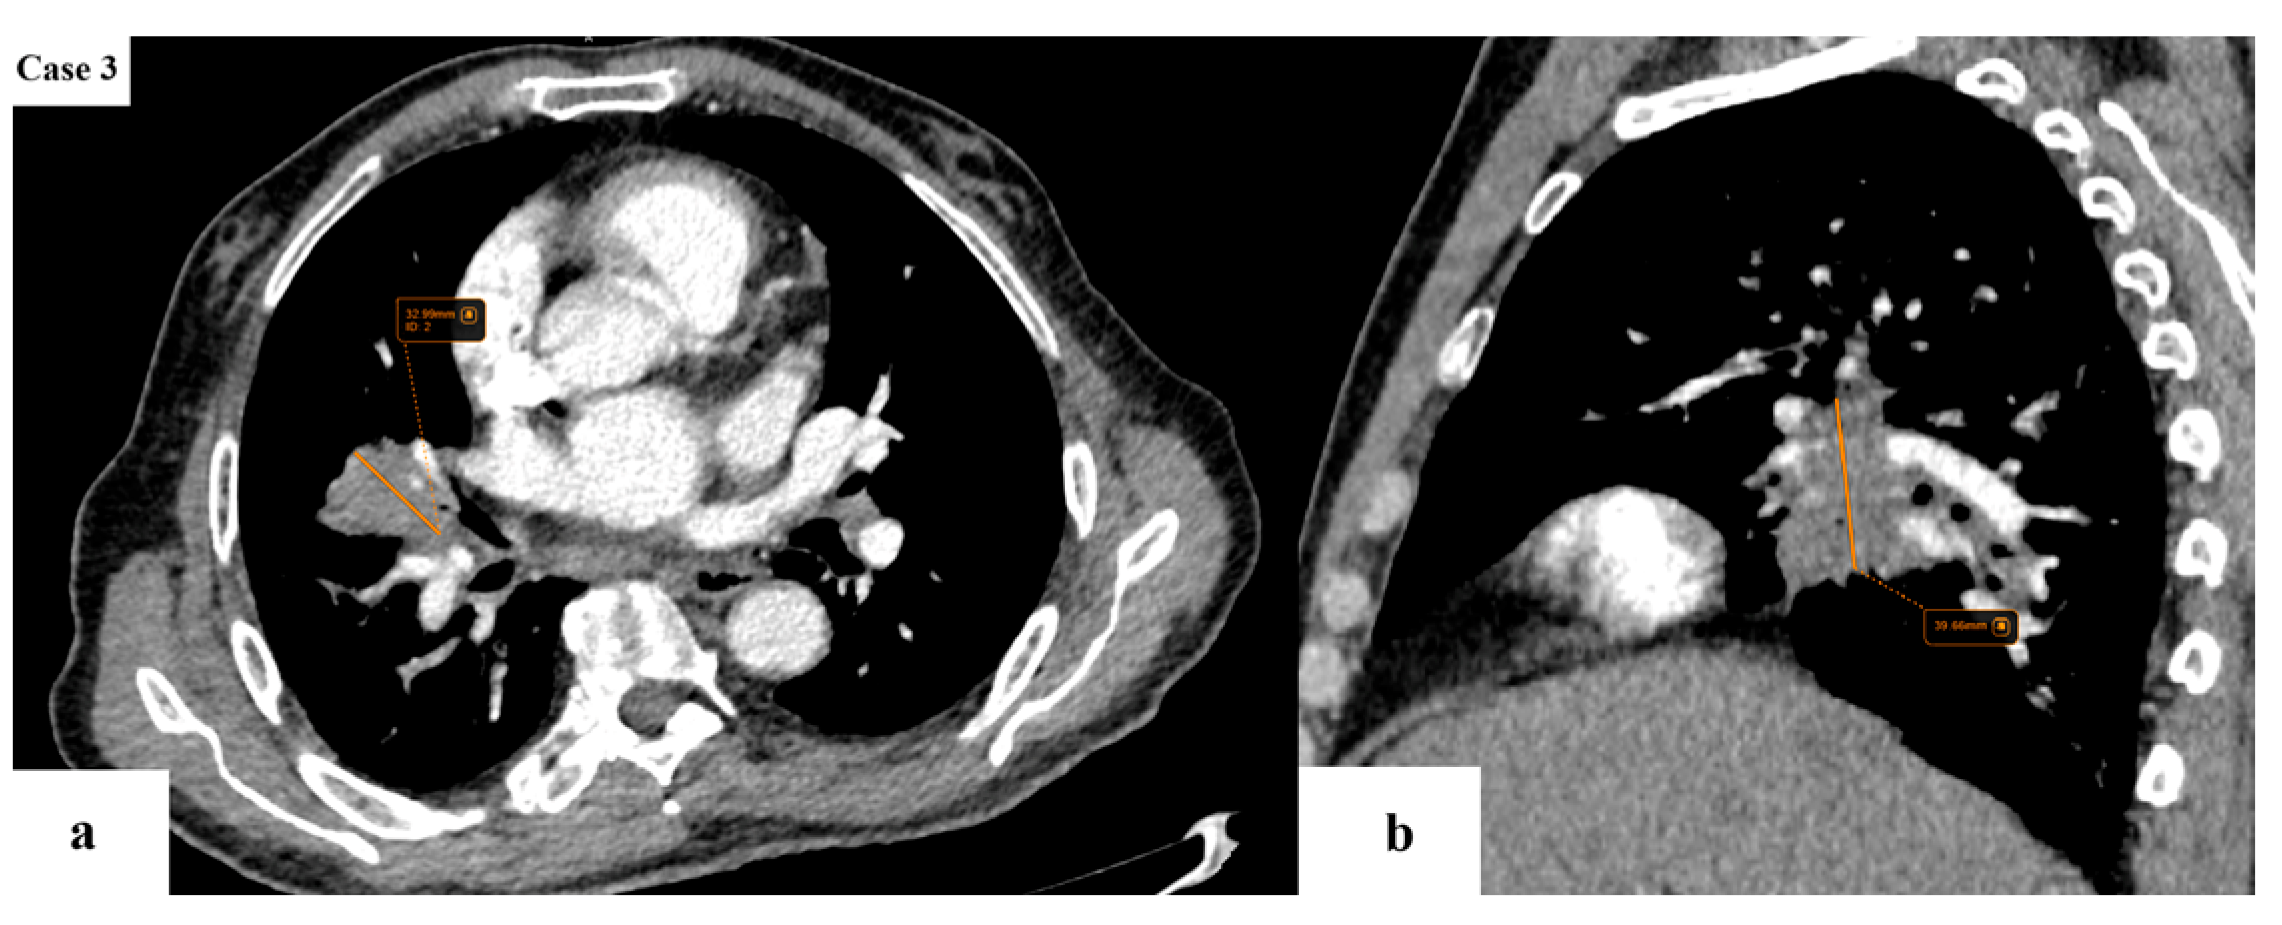

2.2. Data Collection and Imaging Evaluation

2.3. Staging Procedures